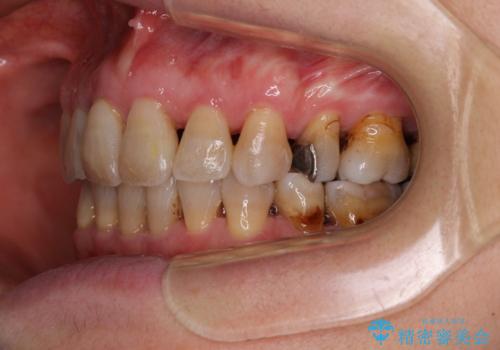

- 突出した口元を引っ込めることを希望して来院された患者様です。

上下左右第一小臼歯4本を抜歯して、口元を改善するワイヤー矯正を行うこととしました。

長年気にされていた口元の突出感が改善されたため、もっと若い時分に矯正をすればよかったと思われていました。